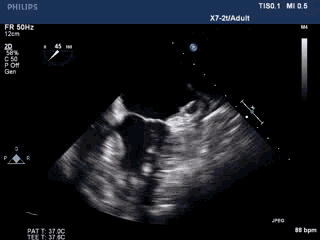

术前准备——TEE评价左心耳结构

左心耳呈多分叶状,口部梳状肌发达。